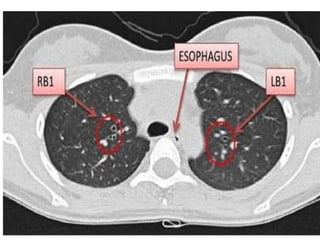

CAÂY PHEÁ QUAÛN VAØ PHAÂN THUØY PHOÅI

+CT cho chi tieát giaûi phaãu toát raát nhieàu so vôùi X

quang qui öôùc

+Phaân tích hình aûnh CT

-Caây pheá quaûn

-Phaân thuøy phoåi

-Raõnh maøng phoåi